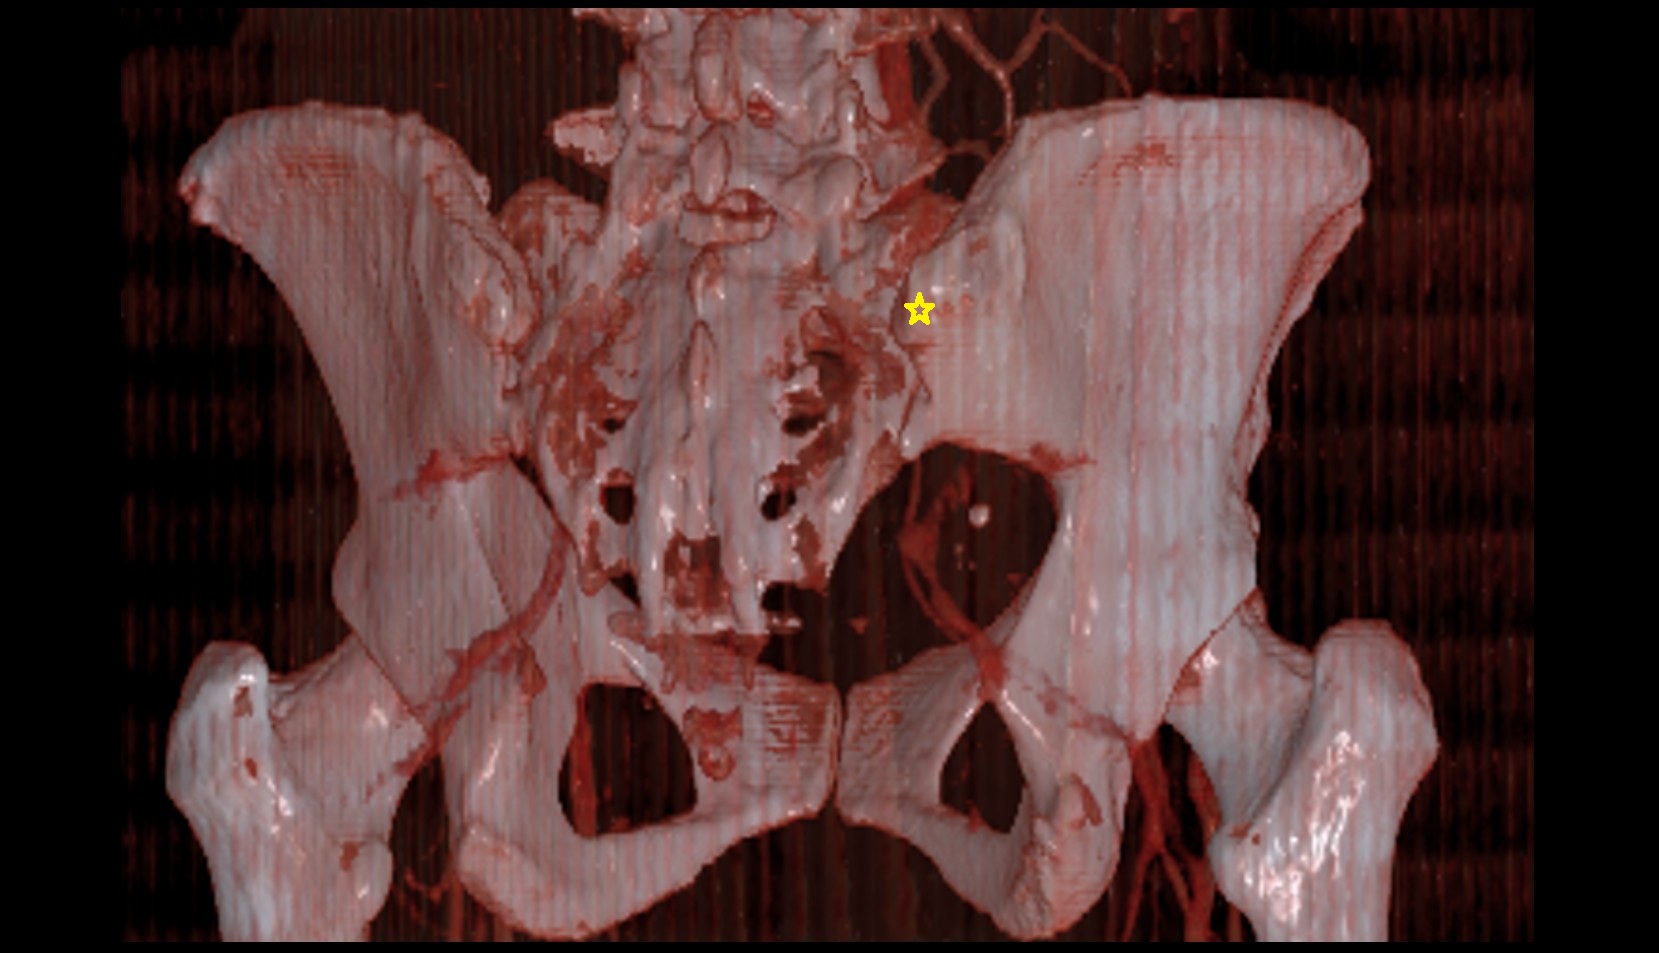

- Sacroiliac joint